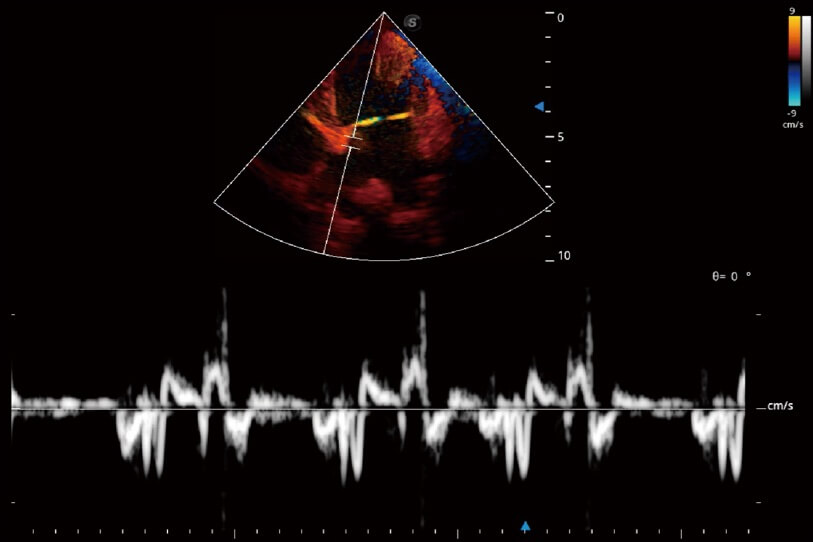

實(shí)時(shí)用顏色表示心肌組織運(yùn)動(dòng),觀察和定量組織的運(yùn)動(dòng)情況,對快速檢測與評估心肌的灌注和活性、電傳導(dǎo)及心肌收縮和舒張功能等均能提供重要的診斷信息。